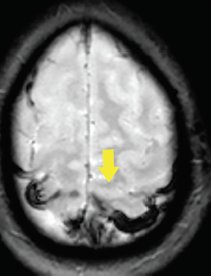

Andrew Henn, DO; Aaron Wolfe, DO; Vikas Jain, MD

A woman presented to the ED after having had a headache for 3 days that she described as a constant, gradually worsening pain.